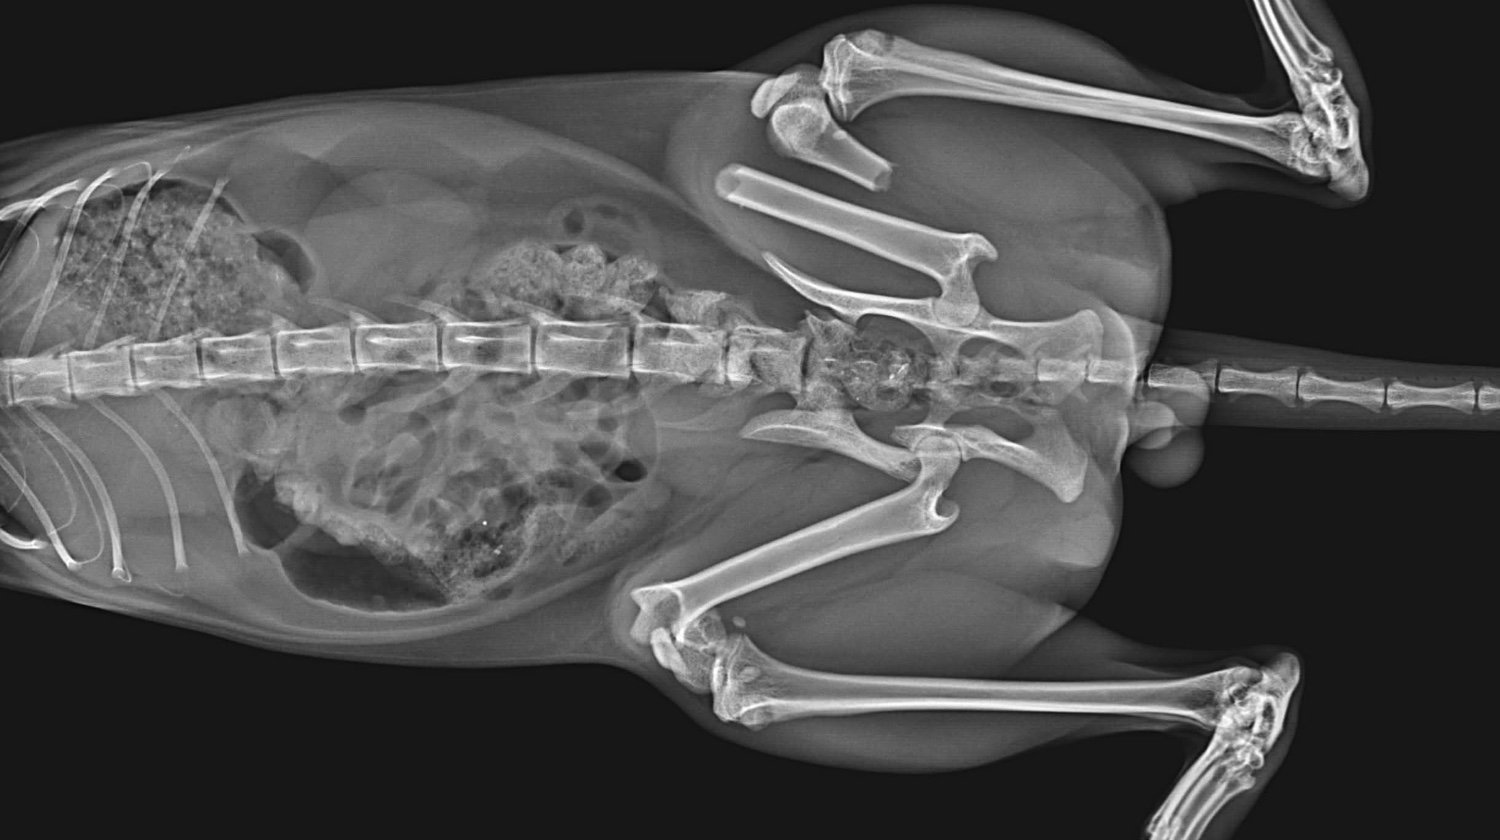

Lucky je maček, ki so ga pred nekaj dnevi našli pred blokom, v katerem živi moj brat. Luckyja je takoj odpeljal k veterinarju. Po posvetu je ugotovil, da ima poškodovani obe nogi in medenico :(. Natančneje, ima naslednje težave:

Medenica

obojestranska sakroiliakalna dismoreksija

Zlom desne iliakalke s premikom

Zadnje okončine

Diafizni zlom v srednji tretjini, poševni, s premikom, brez kostne eklatantnosti, na ravni stegnenice femurulolistangii

Zlom tipa SH I distalno od desne stegnenice

Slikovna diagnoza: zlom leve stegnenice, SH zlom desne stegnenice, obojestranski križno-iliakalni izpah, zlom desne iliakalne palete

Po opravljenih rentgenskih posnetkih, kjer so bile ugotovljene

zgoraj, so ga odpeljali k ortopedu in bo potreboval 3 operacije: po eno za vsako nogo + operacijo medenice.